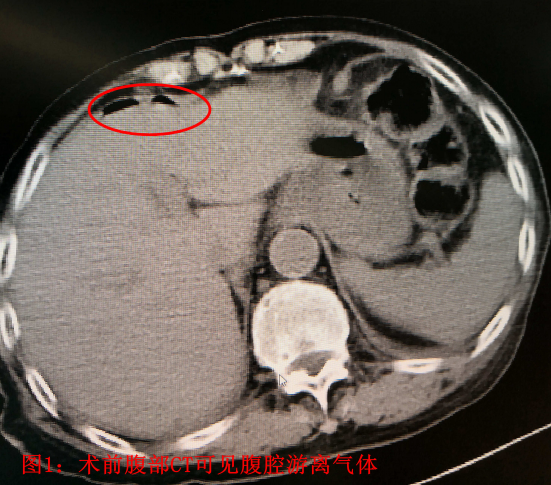

患者:李##,男性,93岁,家住北京昌平天通苑社区,既往患有阿尔兹海默征(俗称“老年痴呆”),无法正常交流。入院前2天出现腹痛、腹胀、恶心、呕吐,自行应用甘油灌肠剂治疗后未见缓解。后出现发热、停止排气排便,就诊于外院,行腹部CT考虑为肠梗阻,给予输液治疗后无效,症状加重,进一步就诊于我院急诊外科,入院时患者神志淡漠,急性痛苦面容,腹部略膨隆,全腹部压痛、反跳痛及肌紧张,患者因不能正常交流,不能描述压痛最重部位。听诊肠鸣音弱。外院腹部CT阅片可见腹腔游离气体,广泛肠道肠壁肿胀,并可见气液平面,考虑为消化道穿孔引起的腹腔感染,并发肠梗阻。血象明显升高(C反应蛋白>200mg/L,白细胞 14.95×10^9/L,中性粒细胞绝对值 12.99×10^9/L,中性粒细胞百分比 87.00%)。因外院腹部CT胶片显示不清,不能明确穿孔部位。急诊复查腹部CT,阅片可见肝周游离气体明确,消化道穿孔诊断明确(见图1。腹腔内肠管肠壁肿胀,可见多发气液平面,考虑为继发性肠梗阻。除外最常见的胃十二场溃疡穿孔及阑尾穿孔。可见左下腹肠道内“枣核”影(见图2,局部肠管肠壁肿胀最明显明显,并可见少量积液。考虑枣核所致小肠穿孔可能大。追问病史家属确认2天前患者进食大枣粥时不慎将枣核吞咽,根据腹部CT提示枣核影位置,反复腹部查体,通过观察患者表情,确认枣核所在部位为压痛最明显部位。综合患者病史、查体及辅助检查结果,考虑患者为肠道异物(枣核)所致小肠穿孔可能性较大。患者如不紧急实施手术治疗,腹腔感染继续加重,会危及老人生命。但患者超高龄,病程较长,全身状况差。心肺脑等重要脏器功能无法完全评估,且患有老年痴呆,围手术期无法配合治疗,围手术期风险极高。充分向患者家属交待手术的必要性及风险后,患者家属表示理解。急诊行手术治疗,术中探查,因患者既往上腹经腹直肌切口下方可见乙状结肠及大网膜粘连,乙状结肠与盲肠、末端回肠及右肝下方粘连,分离粘连,仔细探查腹腔。胃及十二指肠未见明显异常,结肠未见明显病变,距回盲部约160cm处可见小肠局部大量脓苔,肠壁可见异物(枣核)刺穿肠壁(见图34,局部炎症较重,肠壁糜烂,局部腹腔及盆腔可见淡黄色脓液,量约400ml